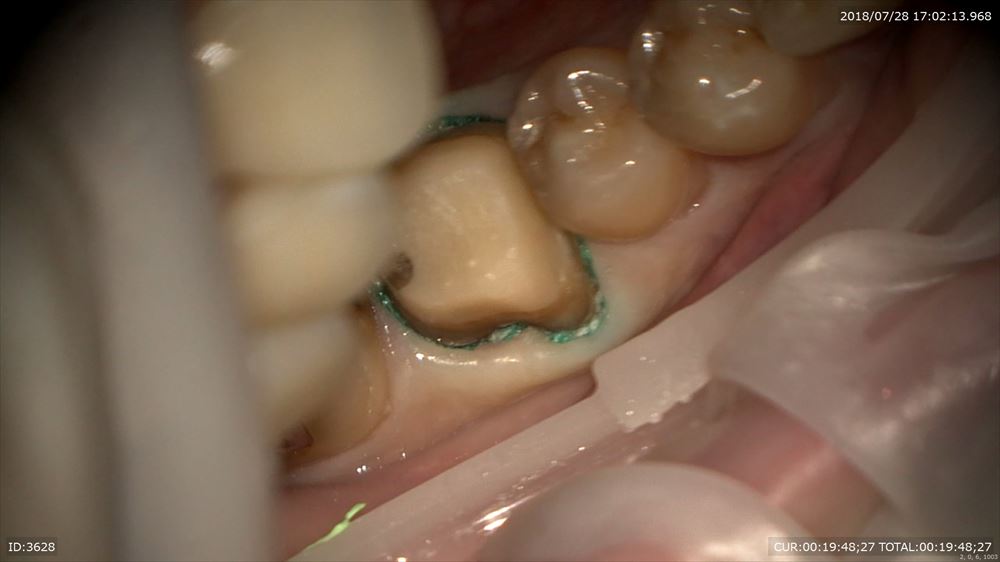

糸を入れるのは隙間を作るから。この緑を外すと

ここ。隙間ができここに型取りの材料を流します。

精密根管治療の予後は精密な型とりと精密な被せ物が重要だと報告があるようにこのステージが大切。